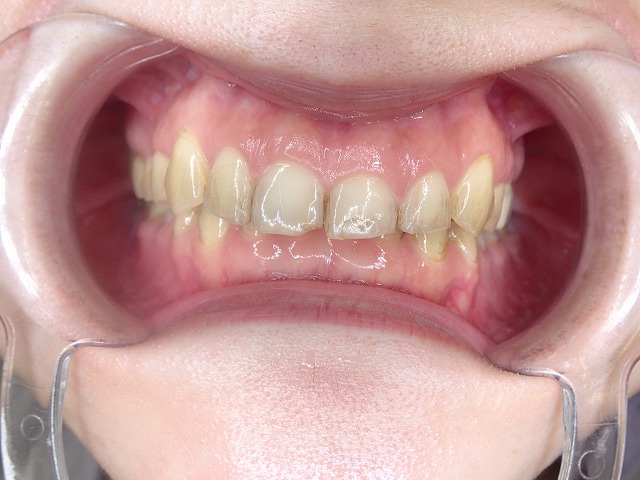

咬み合わせ診査

かなり深い過蓋咬合です。(咬み合わせが深い)

矯正後 過蓋咬合と歯ぎしり もう少し矯正で補正してくれれば

過蓋咬合も歯列矯正で補正できたはず 決して失敗ではないが

過蓋咬合ですので、下の歯に上の歯がかぶさり

下の歯が見えません。

上顎前歯

激しく摩耗している

顎の動きで左右非対称に摩耗しているの

過蓋咬合なので上顎前歯の内側の摩耗が激しい

歯並びが左右非対称